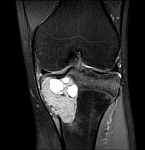

• Resection of benign and malignant tumors of the bone and soft tissue

• Reconstruction of bone defects by biological procedures (from spongiosaplasty to bone transfer)

• Tumor total endoprosthesis (TEP) of all large joints and bones